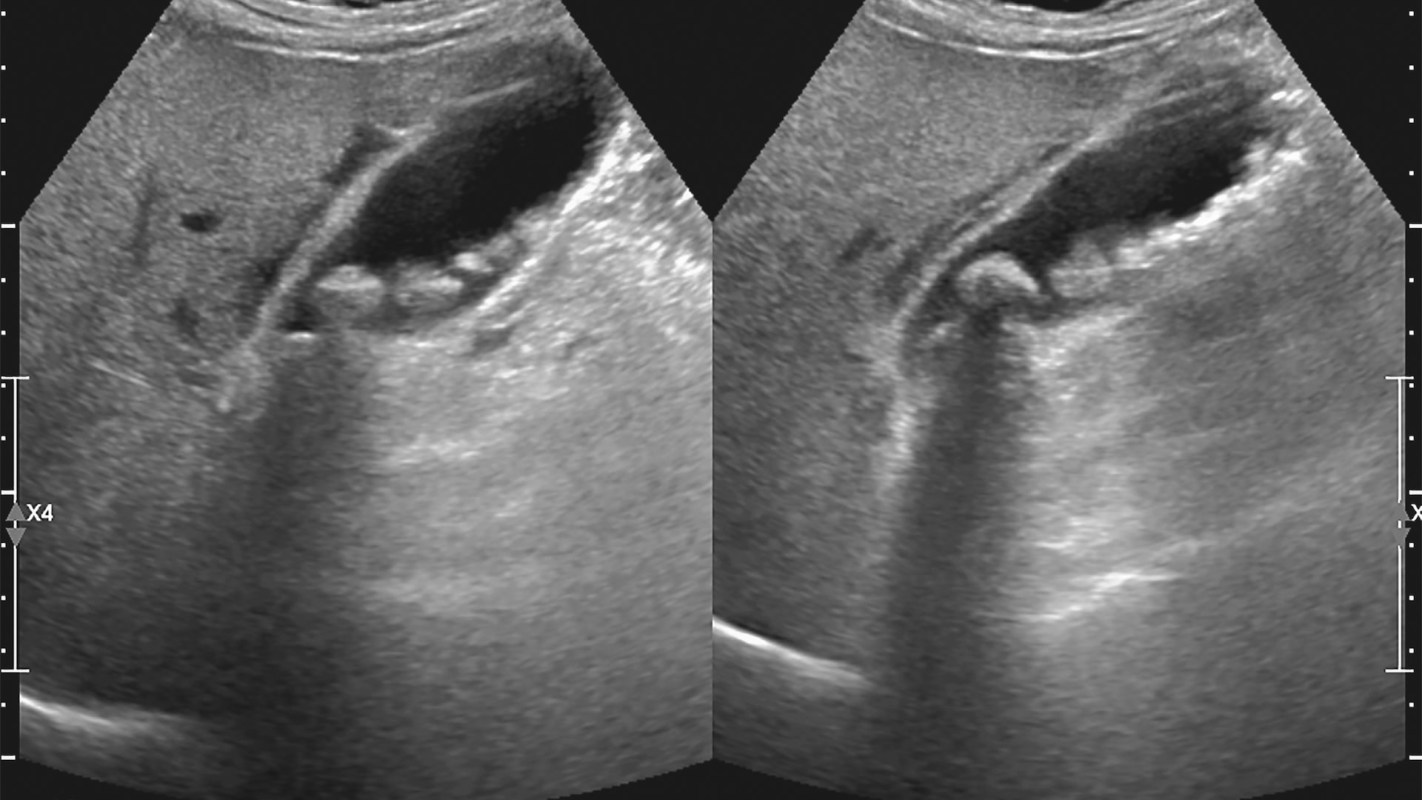

The study links microplastic pollution in rivers, particularly the Ganges, to a rise in gallbladder cancer (GBC) in India.

Researchers from Kerala medical colleges found that microplastics may have carcinogenic effects. These tiny particles can trigger inflammation, oxidative stress, immune system disruption, and gut microbiome changes, factors known to contribute to cancer development.